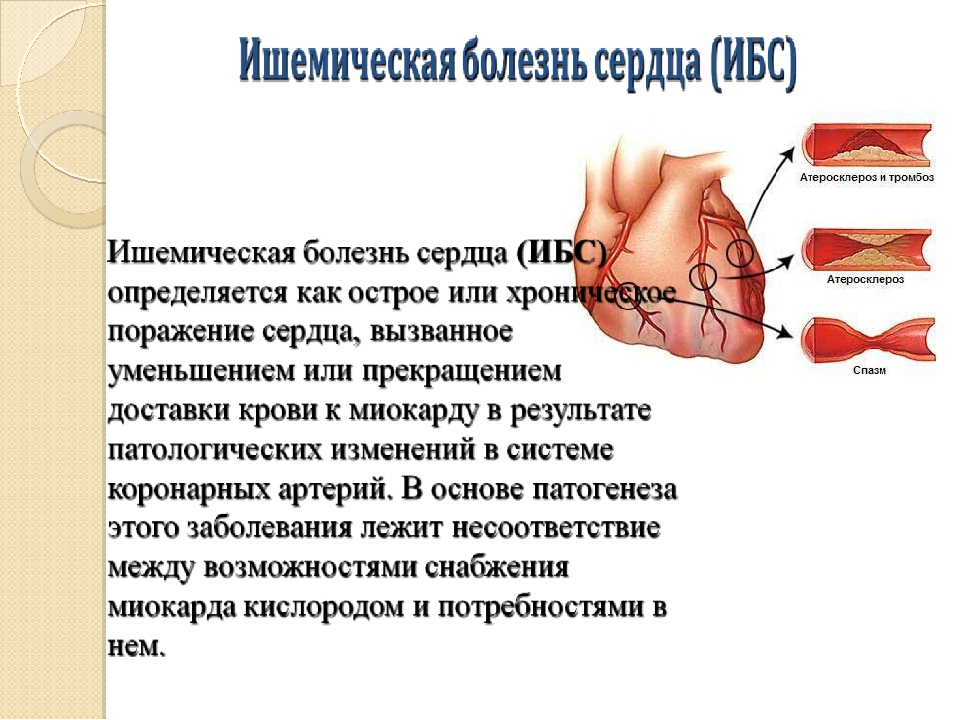

Пороки сердечно-сосудистой системы: виды и признаки